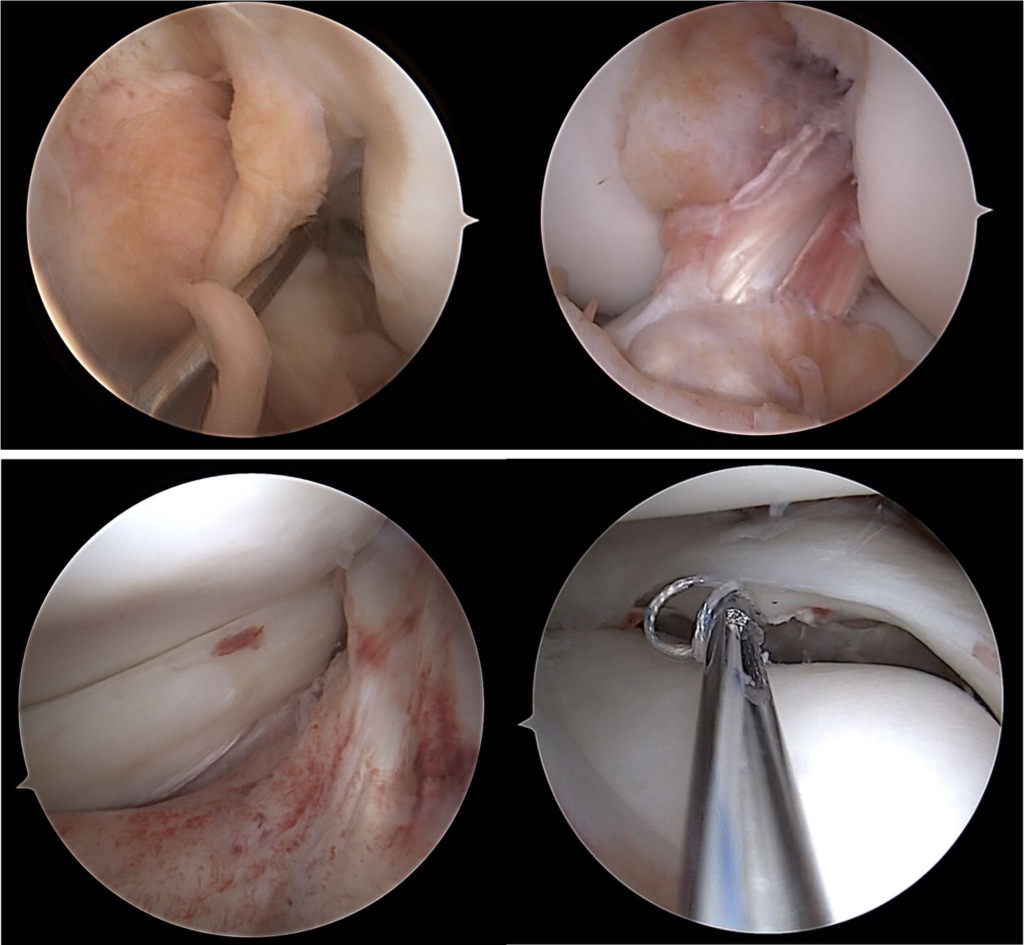

Knee ligament reconstruction

Cartilage restoration

Meniscus surgery

Arthroscopic meniscal repair - (5-50)

Autograft anterior cruciate ligament reconstruction without lateral tendonesis +/- meniscectomy - (5-50)

Multiple ligament reconstruction of knee - (1-5)